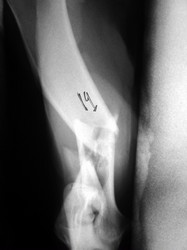

PRÁCTICAS CURSO DE FIJACIÓN EXTERNA PERFECCIONAMIENTO.

Húmero.